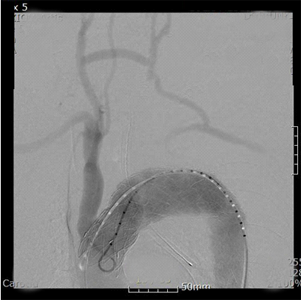

하이브리드 대동맥 수술

술전 CT (대동맥궁 대동맥류) 대동맥내 스텐트 삽입 및 머리혈관 우회술

술전 CT

머리혈관 우회술

술 후 가슴사진 및 술 후 CT

술 후 가슴사진

술 후 CT